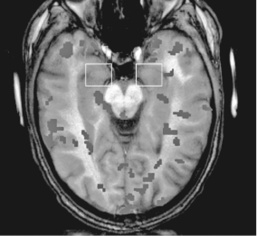

Полученные результаты послужили доказательством непревзойденной гениальности естественного отбора. Они показали значительное увеличение активности как миндалины (участка мозга, который играет ключевую роль в формировании эмоций), так и передней поясной коры (участка мозга, чувствительного к аномалиям). Это происходило в тот момент, когда на записи шли настоящие крики, в отличие от перекодированных фрагментов, и было более характерно для женщин, чем для мужчин. Такая реакция, по мнению Сандер, может отражать врожденную предрасположенность нервной системы женщины реагировать на звуки, издаваемые младенцами, до того как они научатся говорить (см. рис. 2.1 ниже).

Рис. 2.1a. Приблизительная картина областей активности мозга женщины, когда она слышит крик взрослого человека

Рис. 2.1b. Приблизительная картина областей активности мозга женщины, когда она слышит крик младенца

Рис. 2.1c. Приблизительная картина областей активности мозга мужчины, когда он слышит крик младенца

А когда Сандер сравнила активность миндалевидного тела испытуемых в тот момент, когда они слышат крик взрослого и крик ребенка, она испытала настоящее потрясение. Во втором случае активность мозга была в девять раз выше. Крик младенца, вопреки первому впечатлению, далеко не так прост, как кажется.